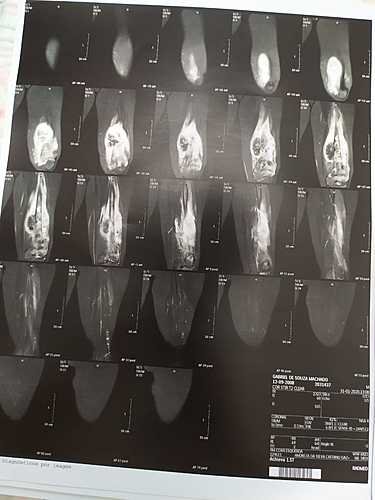

Gabriel De Souza Machado Tem 11 Anos E Devido A Dor E Inchaço Na Perna No Dia 29/01/2020 Fez Um Raio-X Que Detectou Um Tumor Na Perna Esquerda Com 17cm. Outros Exames Foram Feitos E Dia 03/02/2020 Infelizmente Foi Confirmado Um Câncer. Mais Exames Estão Sendo Feitos E Tomografia,Cintilografia, Biópsia. Porém Esses Exames Estão Sendo Feitos Em Minas Gerais Onde Será Dado Inicio Ao Tratamento. Nesse Momento Além Dos Gastos Com Os Primeiros Exames Estamos Tendo Muitos Gastos Com Transporte, Hospedagem E Alimentação. Agradecemos A Todos Que Puderem Ajudar, Não Só Com As Doações Mas Também Orações E Compartilhamento Para Alcançarmos Mais Pessoas

Gabriel De Souza Machado is 11 years old and due to pain and swelling in his leg on 29/01/2020 he underwent an X-ray that detected a 17cm left leg tumor. Other exams were done and on 03/02/2020 Unfortunately a cancer was confirmed. More Exams Are Being Taken And Tomography, Scintigraphy, Biopsy. However, these exams are being done in Minas Gerais where treatment will begin. At this moment, in addition to the expenses with the first exams, we are having many expenses with transportation, accommodation and food. We thank everyone who can help, not only with donations but also prayers and sharing to reach more people